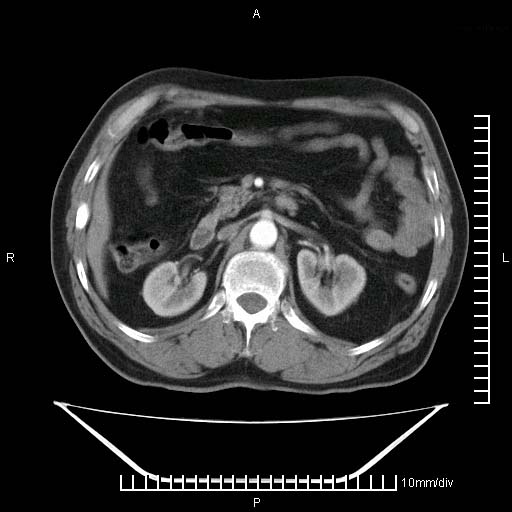

标题: CT25082:肝脏增强:男性,70岁 [打印本页]

标题: CT25082:肝脏增强:男性,70岁

患者以心脏疾病收住院,腹部无明显症状,b超查肝脏有占位。

增强效果不理想。考虑转移,胆囊壁明显增厚,不排除胆囊癌肝转移。

牛眼征,中心坏死无强化,外缘强化,最外缘又见低密度,考虑转移,与脓肿鉴别

肝内多发转移瘤,右下肺炎症并少量胸水。胃壁增厚建议胃镜,胰尾部“病变”为肠管。

1)肝脏多发性转移瘤(不排除胰尾癌转移所致可能)。2)腹水。3)右侧少量胸腔积液。

ct25082 结果:转移瘤

外院mr结果:胰尾恶性占位。